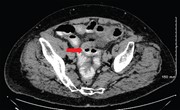

Acute rectal ischaemia following emergency abdominal aortic aneurysm surgery

Frances R. Mosley and others

Journal of Surgical Case Reports, Volume 2016, Issue 10, October 2016, rjw172, https://doi.org/10.1093/jscr/rjw172